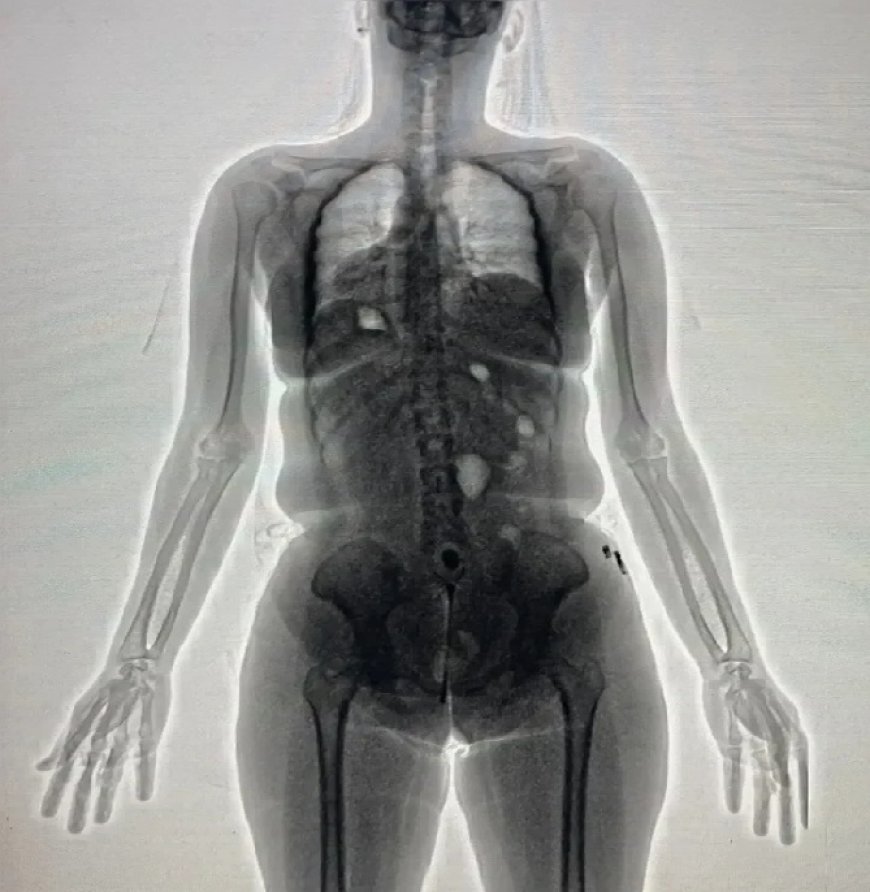

Uma mulher foi presa em flagrante na manhã desta terça-feira (6) após tentar entrar no Conjunto Penal de Barreiras, no oeste da Bahia, com drogas escondidas em suas partes íntimas. O caso foi descoberto durante a inspeção de rotina realizada com o auxílio do scanner corporal (bodyscan), equipamento utilizado para identificar materiais ilícitos que possam ser introduzidos na unidade prisional.

De acordo com a Secretaria de Administração Penitenciária (Seap), as imagens geradas pelo bodyscan apontaram uma anormalidade na região pélvica da visitante. Ao ser questionada por agentes femininas, ela confessou que transportava aproximadamente 20 gramas de substância análoga à maconha e cocaína, escondidas na vagina.